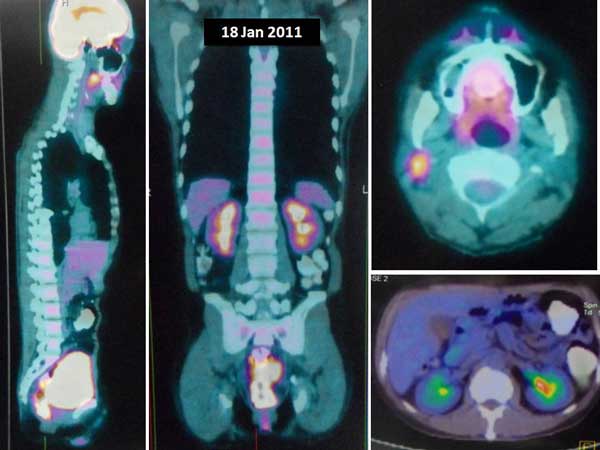

I had a chance to talk to his doctor who told me my brother had anaplastic thyroid cancer. In addition, there were extensive metastases in his lungs and liver. Without doubt – by just looking at the CT scan images (below) – I knew that his days were numbered. No treatment would be able to save him.

On top of this aggressive, rare cancer he also had metastases in his lung and liver. His metastasis was very serious indeed. There is no way anyone can pretend to be a “hero” trying to save him. Added to that was the metastasis to the liver. I was not able to know how extensive it was because I was not able to see the CT scan of his liver.